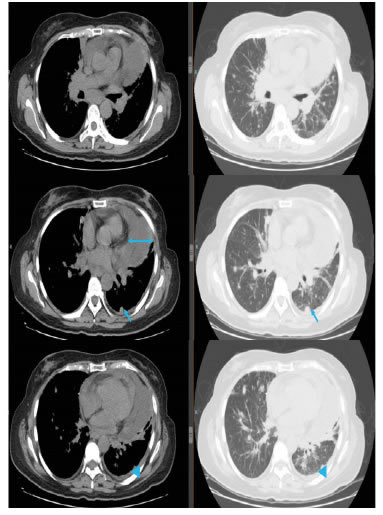

Se trata de una mujer de 38 años con cáncer bilateral de mama, sincrónico, triple negativo y localmente avanzado, que recibió quimioterapia neoadyuvante y, posteriormente, se sometió a mastectomía radical bilateral modificada de tipo Madden, y radioterapia posoperatoria. La reconstrucción mamaria fue tardía y por etapas.

Tuvo un periodo de dos años libre de enfermedad y, durante su vigilancia y seguimiento, refirió disnea progresiva de medianos esfuerzos y de un mes de evolución. El índice de Karnofsky fue de 70 % y presentó taquicardia sinusal.

En el electrocardiograma se encontraron signos de bajo voltaje y ausencia de la onda p. En la radiografía de tórax se observó ensanchamiento de la silueta cardiomediastínica y borramiento del ángulo costofrénico izquierdo (figura 1). En la tomografía de tórax (TC), se observó un derrame pericárdico con separación de 3,5 cm entre las hojas del pericardio y un derrame pleural izquierdo (figura 2).

Se realizó una ventana pericárdica más pericardiectomía e instalación de un catéter pleuro-pericárdico subcutáneo (tunnelized) mediante toracoscopia izquierda. El líquido pericárdico era de color cetrino. No se identificó carcinomatosis pleural o pericárdica. El examen citológico del líquido pericárdico fue negativo para neoplasia maligna y en la histopatología de las biopsias de pericardio y de pleura parietal se observó un mesotelio reactivo, negativo paraneoplasia maligna (figura 3).

El drenaje pleuro-pericárdico temporal se mantuvo durante tres semanas hasta que los gastos fueron menores de 50 ml. La radiografía de tórax mostró la posición del catéter pleuropericárdico, una adecuada expansión pulmonar izquierda y disminución del tamaño de la silueta cardiomediastínica (figura 4). La paciente recibió rehabilitación cardiopulmonar (figura 5).

En la evaluación ecocardiográfica de la función ventricular, la fracción de eyección fue de 55 % y hubo signos de insuficiencia cardiaca asociados a cardio-toxicidad.